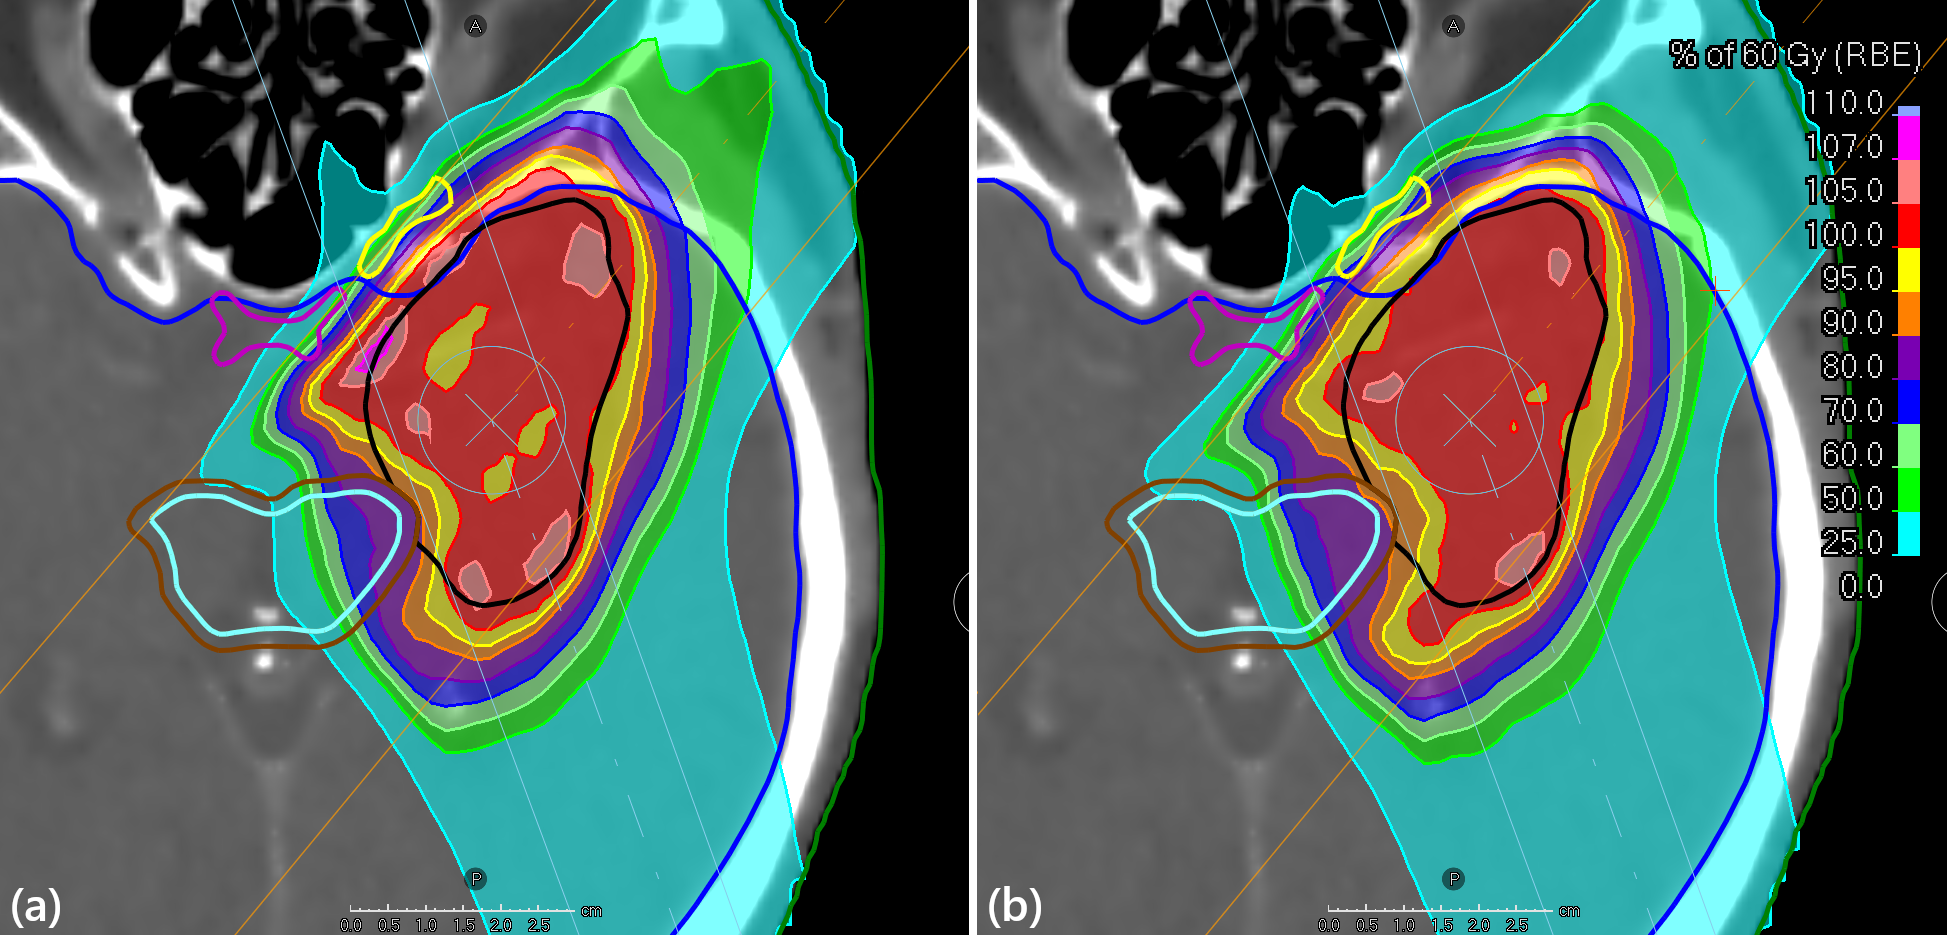

Figure 3: Transversal slices and dose distributions of the prostate case treated with VMAT for (a) the probabilistic method and (b) the conventional margin-based method. ROIs displayed are CTV (black), CTV + 0.7 cm margin (white), rectum (brown), bladder (yellow), anal canal (cyan), bulbus (magenta), external (green).

The dose–volume histograms (DVHs) in Figure 2 illustrate these differences, showing lower OAR doses and maintained target coverage in the probabilistic plan and the dose distributions in Figure 3 show that it has slightly retracted the high-dose region away from the rectum.

Figure 4 shows that the DVHs of the OARs of the probabilistic plan were generally lower than those of the conventional plan, and that the CTV coverage was slightly higher. The dose distributions in Figure 5 show that the probabilistic plan retracted the dose away from the inside of the brainstem but had higher doses just outside of it than the conventional plan. It also used the anterior beam more than the conventional plan, and had more heterogeneous nominal target dose.